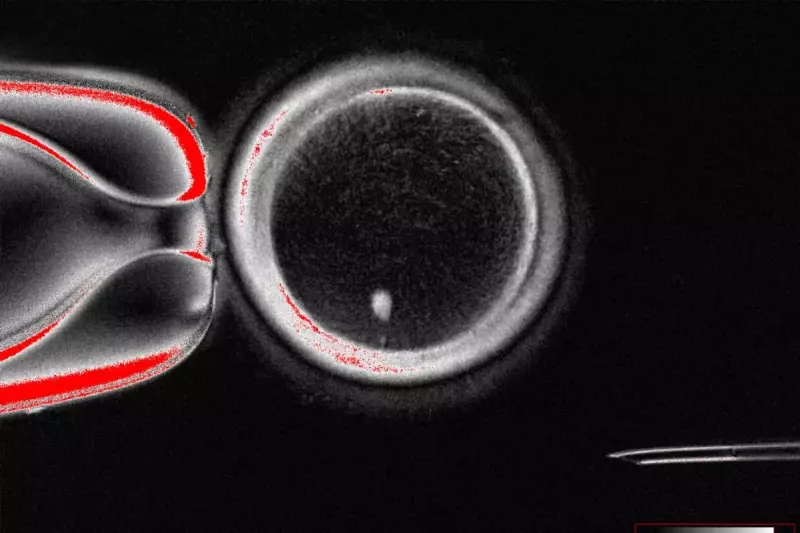

The research team employed cutting-edge imaging technology to observe the earliest stages of embryonic development in real-time, tracking the critical changes that occur within the first 96 hours after fertilisation.